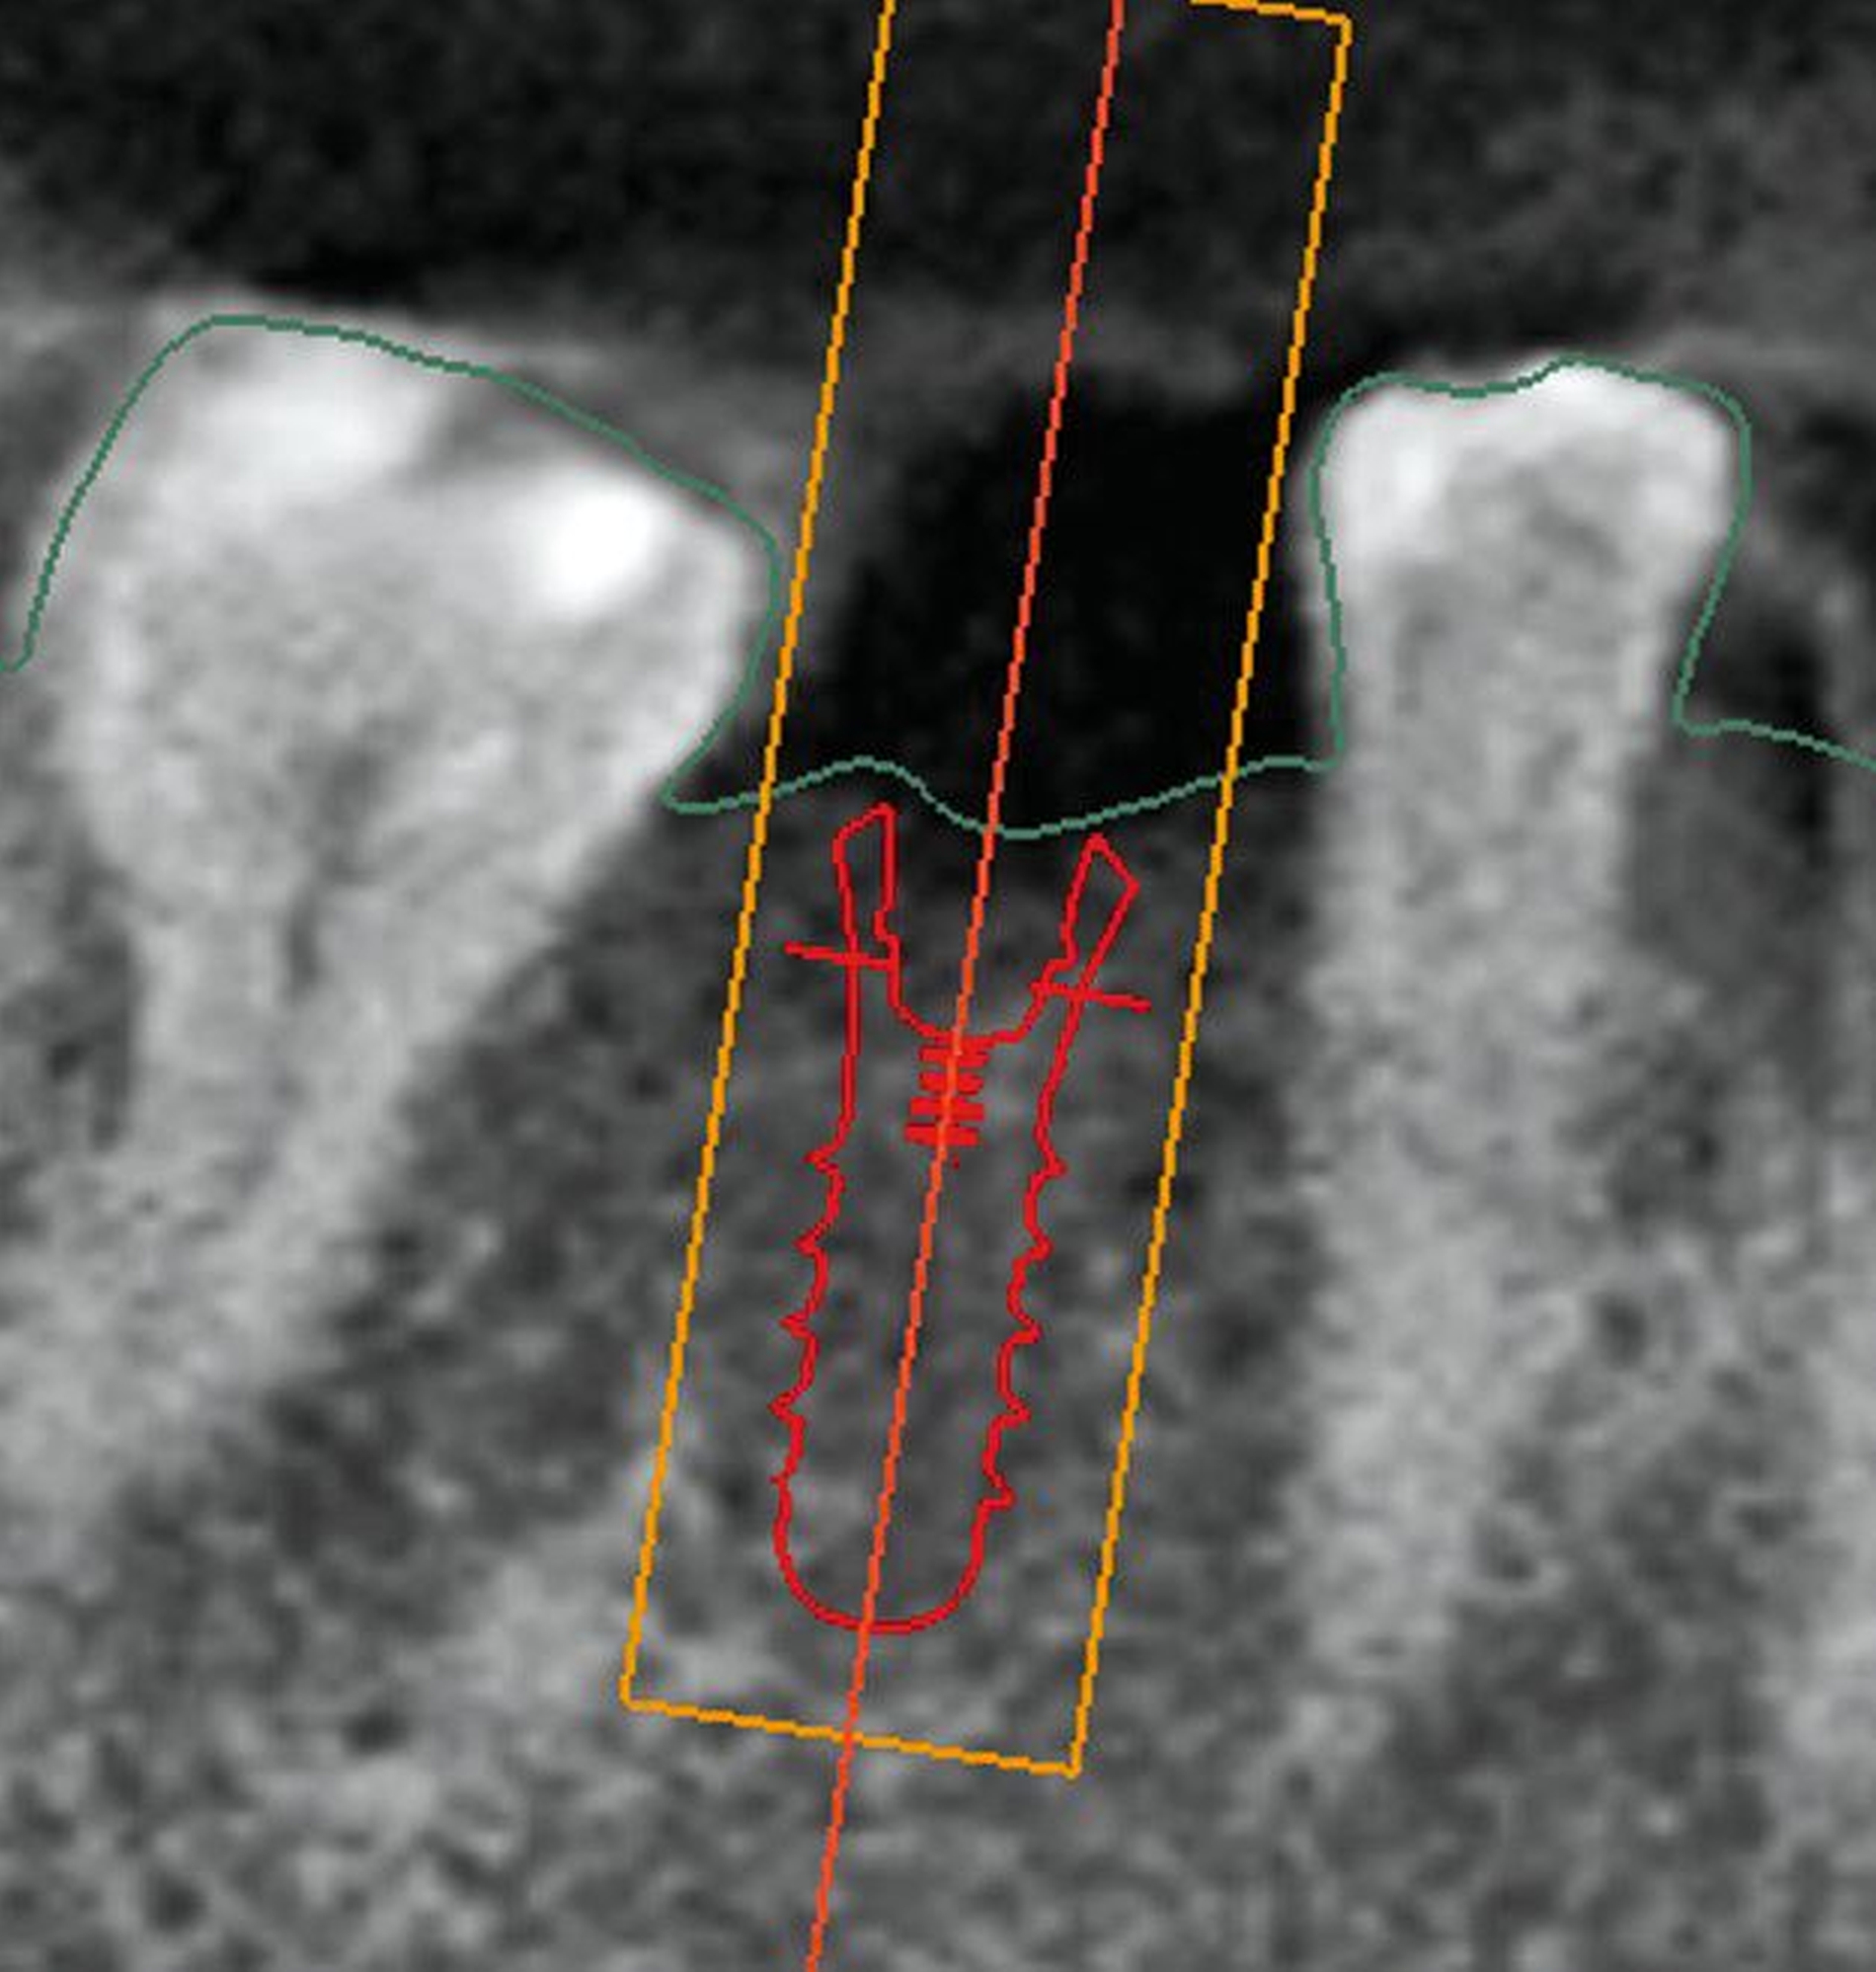

Das International Team for Implantology (ITI, Basel, Schweiz) hat sich der Klassifikation von Implantatsituationen gewidmet und eine im Alltag sehr gut anwendbare Einschätzung vor Behandlungsbeginn etabliert. Dabei werden laut SAC Assessment Tool drei Kategorien unterschieden: straightforward (S), advanced (A) und complex (C). Am Beispiel eines relativ einfachen Falles mit fehlendem Unterkiefermolar (Zahn 46) werden die verschiedenen Einflussfaktoren besprochen. Anschließend werden die klinisch relevantesten Schritte des komplexen zweiten Falles separat grafisch dargestellt.

Chirurgische Klassifikation

Als nächster Punkt wird der Zugang zum OP-Gebiet beurteilt. Liegt keine Einschränkung vor, befinden wir uns im S-Bereich. Die beiden nächsten Punkte betreffen Pathologien an den Nachbarzähnen und vorige Operationen im Implantationsgebiet. Die einfachste Situation ist, wenn weder Pathologien noch irgendwelche Voroperationen vorliegen. Bei der Beurteilung der chirurgischen Komplexität spielt die Ausheilung des Knochens eine Rolle, wobei die Implantation in eine ausgeheilte knöcherne Situation ohne Knochen-aufbauende Maßnahmen den einfachsten Fall darstellt.

Dann wird der Status der Weichgewebe erfasst und beurteilt: Bei einer Breite von mehr als 4 mm keratinisierter Mukosa ohne Narbengewebe und Entzündungen wird das Label S vergeben. Die Nähe von anatomischen Nachbarstrukturen ist der nächste Punkt, im S-Fall besteht nur ein minimales Risiko der Beteiligung. Das Vorhandensein der Papille an den Nachbarzähnen ohne Rezessionen stellt die ideale Situation dar. In der S-Variante befindet sich das Knochenniveau der Nachbarzähne auf der Höhe der Schmelz-Zement-Grenze, wobei ein gewisser Knochenabbau im Zusammenhang mit dem Verlust eines Zahnes einzurechnen ist.